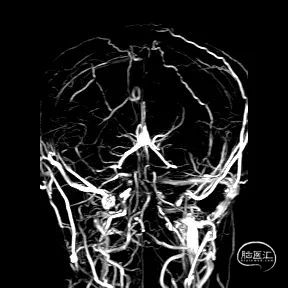

术前CTA/CTP检查,动脉成像未见明显异常,平扫CT可见右侧横窦区域高密度、左侧顶叶片状高密度,窦汇区域、上矢状窦区域高密度充盈。随后紧急性头颅MRV检查,MRV提示上矢状窦及右侧横窦区域不显影。

图注1:1A/1B 平扫CT可见右侧横窦、窦汇区域高密度,额顶叶片状高密度灶

1C 通路CTA检查动脉像未见特殊

1D/1E MRV冠状位及侧位可见上矢状窦及右侧横窦消失,左侧横窦乙状窦部分显影